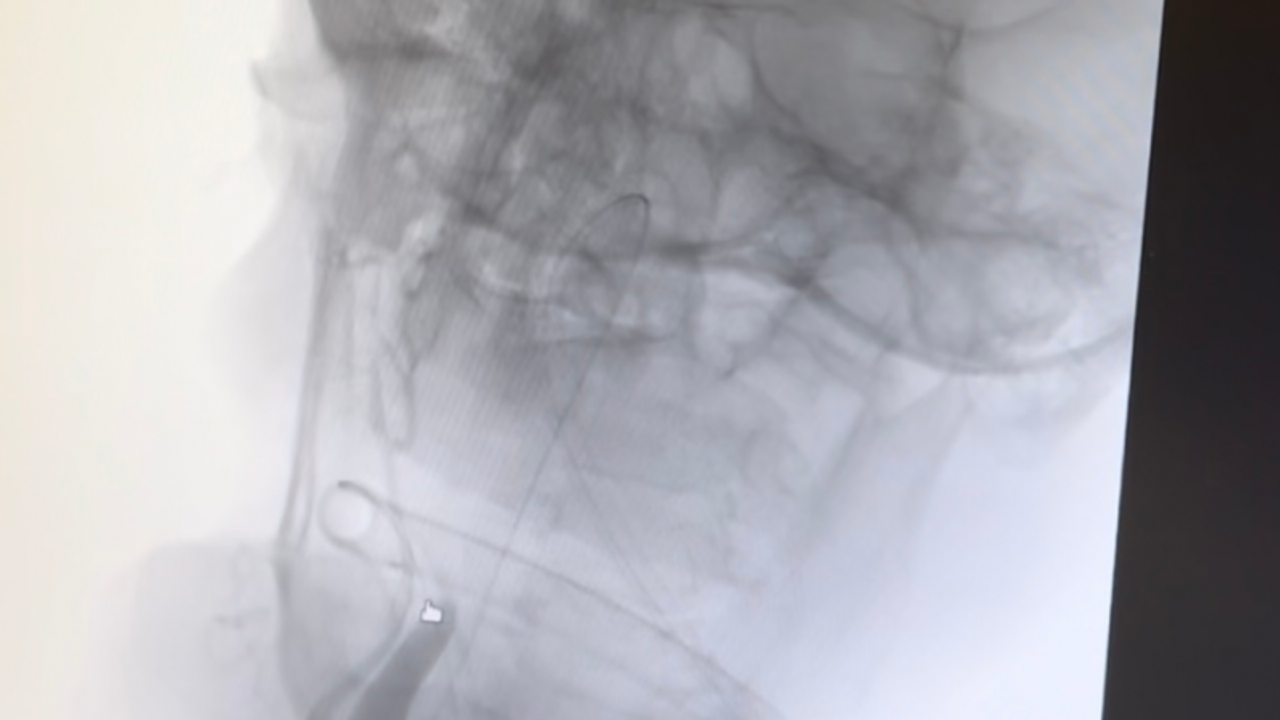

İnme semptomlarıyla hastaneye başvuran Sezer’in sağ kol ve bacağında güçsüzlük, konuşma bozukluğu ve bilinç bulanıklığı şikâyetleri bulunuyordu. Yapılan görüntülemeler sonucunda hastanın şah damarında tıkanıklık tespit edildi. Girişimsel Nöroloji Uzmanı Doç. Dr. Ezgi Sezer Eryıldız tarafından anjiyo ünitesinde acil olarak uygulanan trombektomi (damar tıkanıklığına yol açan pıhtının cerrahi olarak çıkarılması) işlemiyle hastaya müdahale edildi.

“Hastamız bize erken saatlerde ulaştı. Bilinç bozukluğu, konuşma sorunu ve bir tarafında güç kaybı vardı. Görüntüleme sonucunda şah damarında tıkanıklık olduğunu gördük ve hemen müdahale ettik. Trombektomi işleminin ardından dakikalar içinde felç belirtilerinin gerilediğini gözlemledik. Ardından inmenin nedenine yönelik tetkiklerimizi yaptık ve hastamızın tedavisini düzenledik. Şu anda günlük yaşamına bağımsız bir şekilde devam ediyor.”